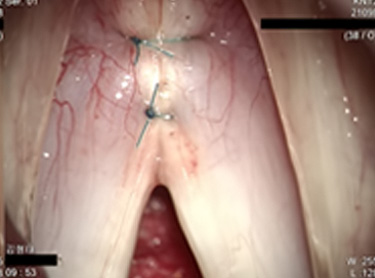

제거한 후 영구적인 실을 사용하여 꿰매는 방법입니다.

양쪽 성대 근육의 앞쪽 부분을 꿰맨 후 매듭을 집니다.

수술 1년 후 성대